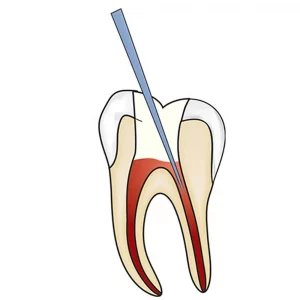

The GDC Conservative Kit Instruments Set of 19 in Pouch (CIP19) is a comprehensive set of dental instruments designed for conservative dental procedures such as fillings, extractions, and other restorative treatments. The kit includes 19 essential instruments made of high-quality stainless steel, all neatly arranged in a convenient pouch for easy storage and transport. This kit is ideal for dentists and dental professionals who want a reliable and complete set of instruments for conservative dental procedures. The instruments are designed for precision and durability, ensuring consistent and efficient performance during every procedure. The pouch also makes it easy to keep the instruments organized and within reach, making it a practical choice for both mobile and stationary dental clinics.